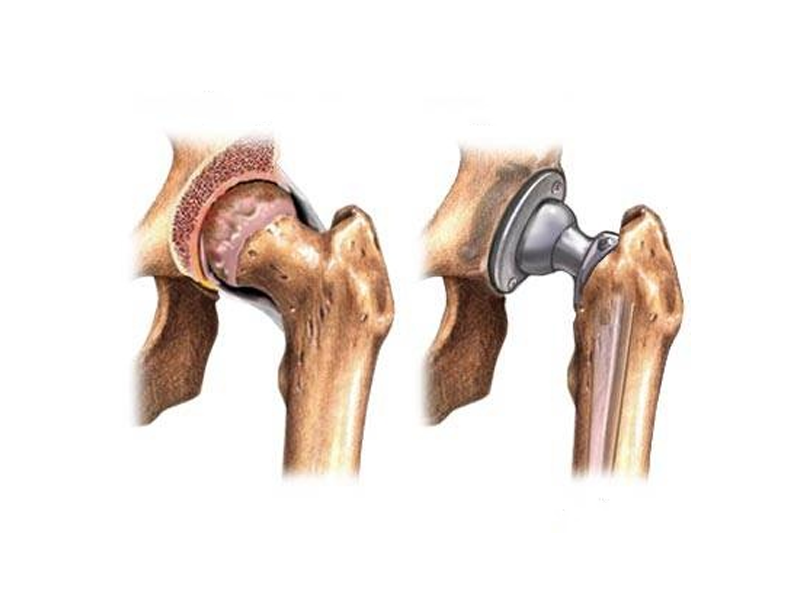

تصور کنید دوباره راحت و آزادانه قدم بزنید، بدون اینکه دردی احساس کنید یا درد شما را ناراحت کند! جراحی تعویض مفصل یا آرتروپلاستی، همان شاهکار در دنیای پزشکی است که مفاصل فرسوده را با پروتزهای پیشرفته جایگزین میکند و سلامت را به زانو، شانه